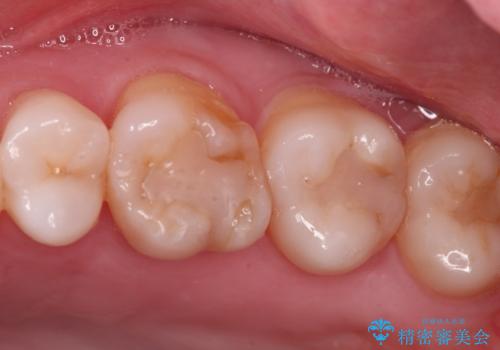

- 銀歯をやりかえたいが他院で抜歯と言われセカンドオピニオンで来院。適合の悪い被せ物が入っており、まずは古い材料、虫歯をとり保存可能か確かめる必要があり、拡大鏡下で全て取り除いたら歯質が歯茎の中まで虫歯がありました。このまま無理やり型取りをして被せ物を作っても不適合な被せ物が入る可能性が高いため歯茎を切り取る手術(ディスタルウェッジ)を行いました。そして再根管治療を行いゴールドの被せ物で治療を行いました。

適合の良い被せ物が入り大変満足して頂けました。